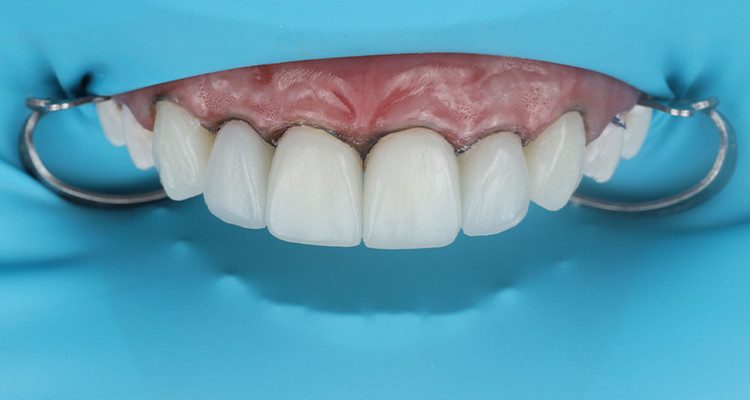

11 | Aspecto final das restaurações após acabamento e polimento.

“A resina Vittra APS faz parte da minha rotina clínica em diversas situações durante o dia a dia, em especial para a última camada de dentes anteriores. Com ela, consigo uma excelente esculpabilidade, o que facilita a escultura e minimiza a chance de erros, além de seu ótimo polimento que se mostra estável com o passar dos meses!”